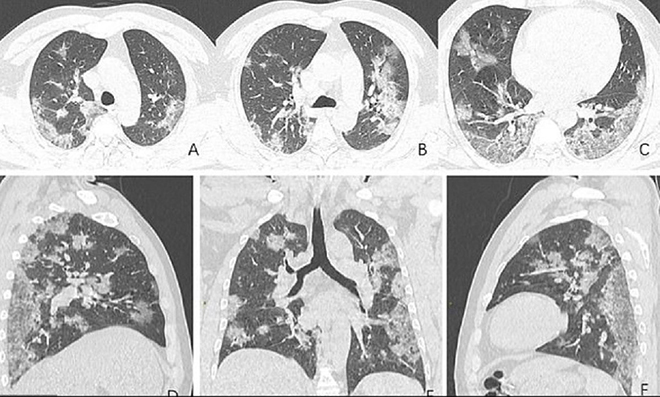

Merkezi ABD’de bulunan Kuzey Amerika Radyoloji Topluluğu tarafından paylaşılan röntgen görüntüleri corona virüsünün ciğerlere nasıl etki ettiğini gözler önüne serdi. Uluslararası basın kuruluşlarına yansıyan görüntülerde Whan’daki deniz ürünleri pazarında çalışan 44 yaşındaki bir corona virüsü hastasının ciğerlerindeki doluluk oranı görülüyor.

Yapılan açıklamada röntgeni çekilen 44 yaşındaki hastanın 25 Aralık 2019’da hastaneye öksürük ve yüksek ateş dolayısıyla gittiği ve tedavi altına alındığı belirtildi. Yetkililer doktorların müdahalesine rağmen hastanın bir hafta sonra öldüğünü aktardı.

İngiliz tabloid gazetesi Daily Mail’deki haberde Wuhan’a gittikten sonra hastalanan 54 yaşındaki bir kadının da ciğer röntgenleri paylaşıldı. Hastanın yüksek ateş, öksürük, halsizlik ve göğüs ağrısı şikayetiyle hastaneye gittiği belirtilirken, hastaya oksijen ve antibiyotik verildiği belirtildi. Japonya’ya döndükten sonra hastanın ilaç tedavisiyle birlikte iyileştiği açıklandı. Haberde, bu tür değişikliklerin SARS ve MERS hastalardakilerine benzediği belirtildi.